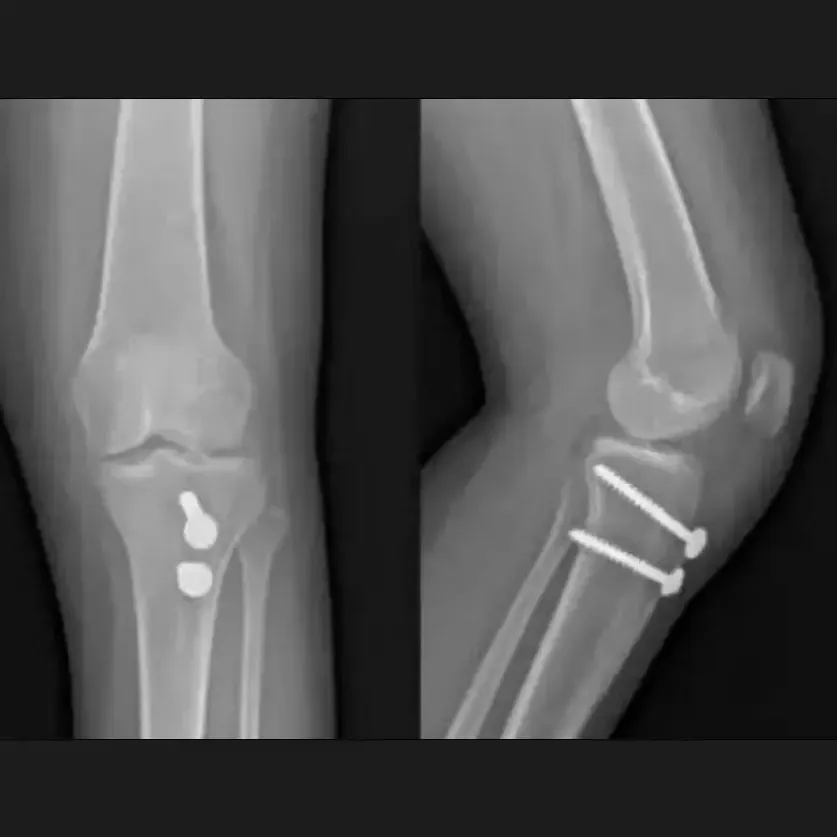

Fracturas intraarticulares de rodilla

Fracturas que comprometen la articulación de la rodilla, como fémur distal, tibia proximal o rótula.

Procedimientos: Fijación con placas, tornillos o reemplazo articular.

Fijación de fracturas de rodilla

Descripción: Reparación quirúrgica de fracturas con placas y tornillos.

Indicado para:

• Fracturas de rótula, fémur distal o tibia proximal.